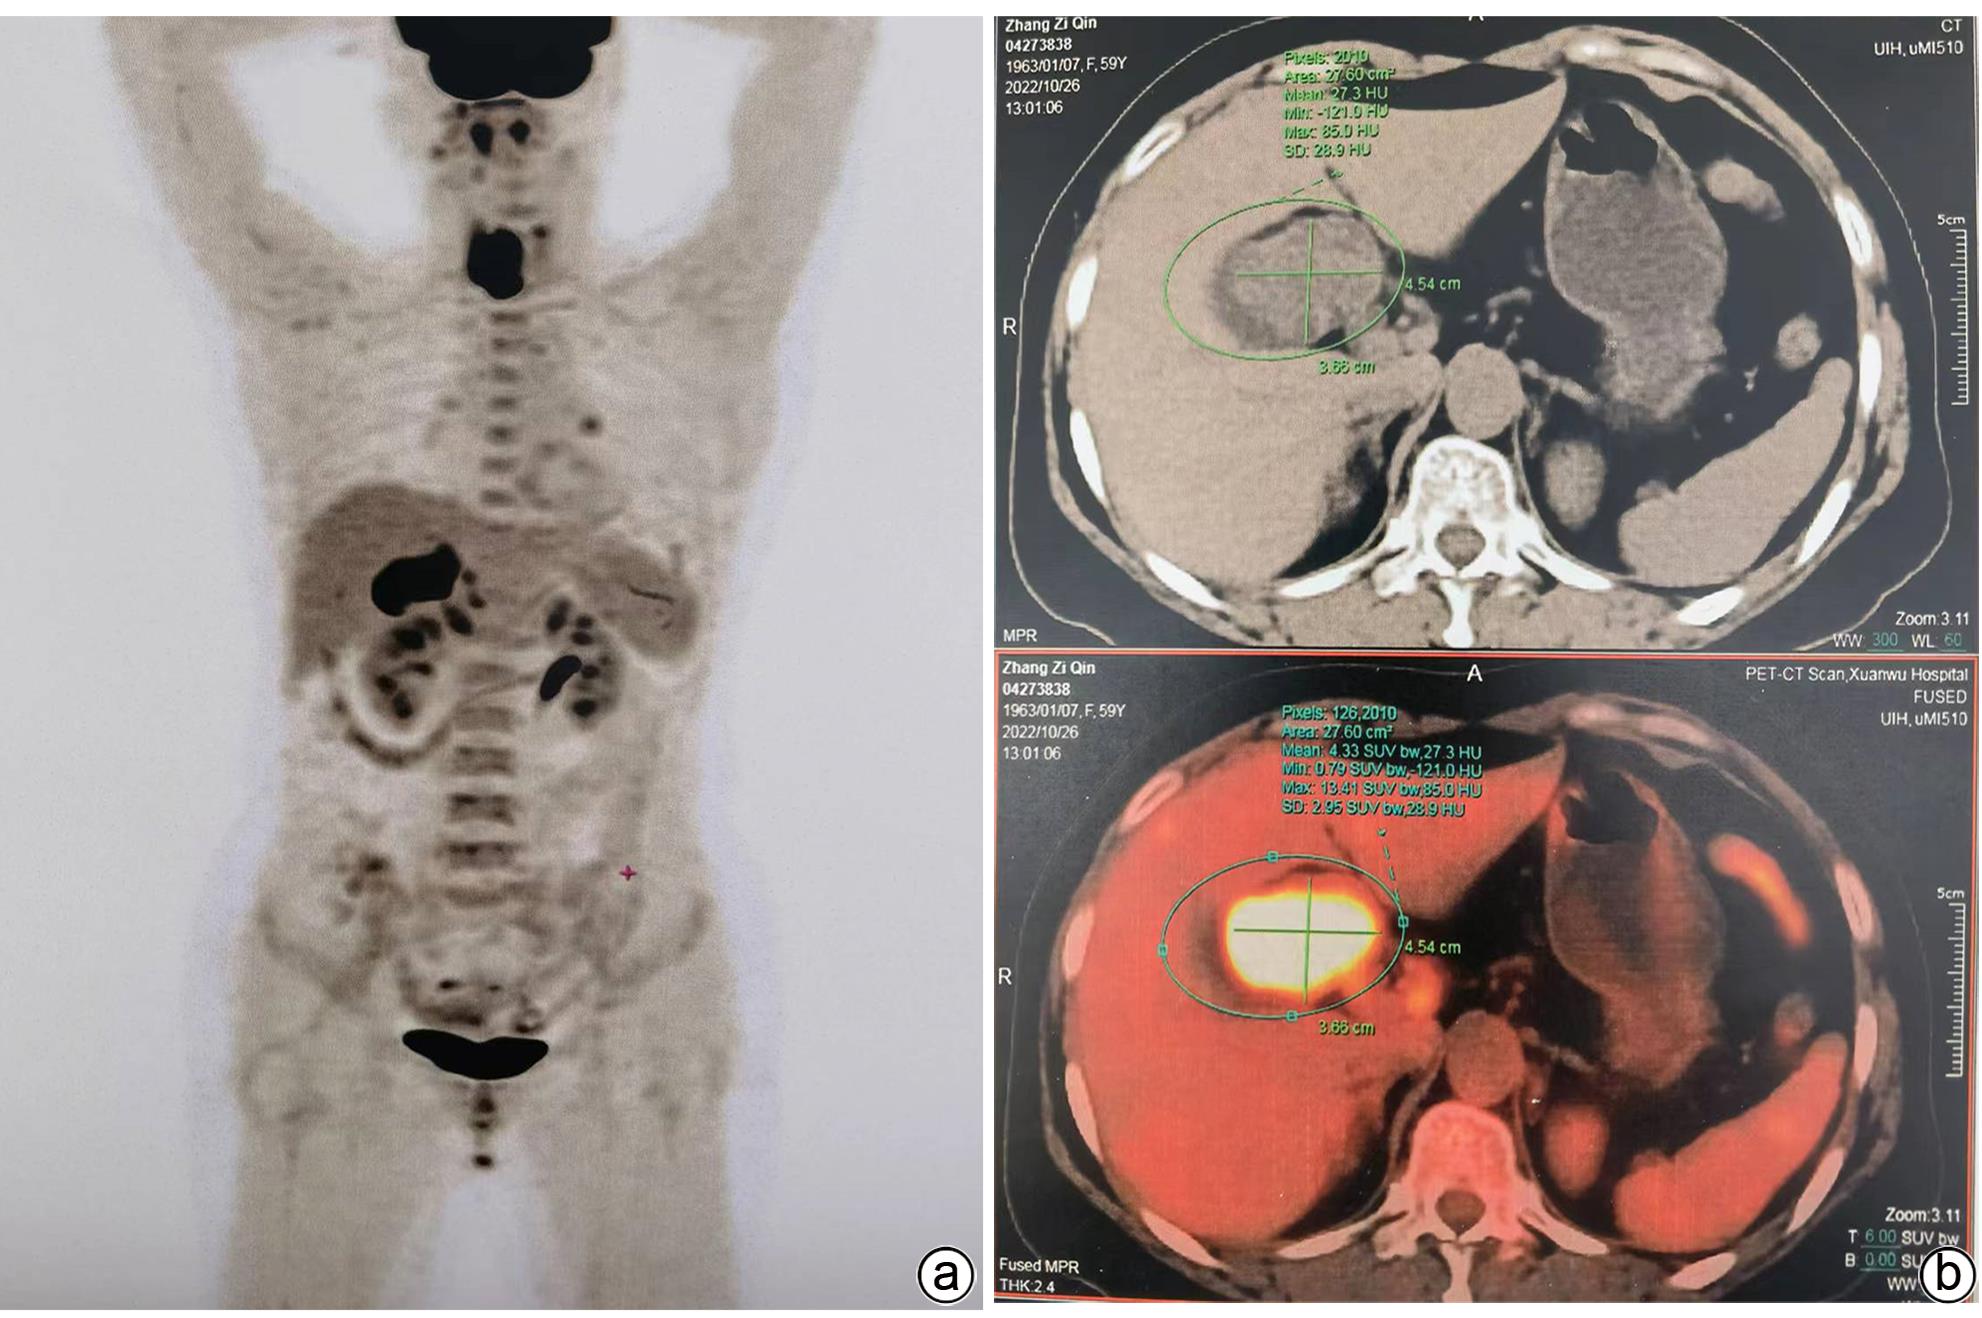

1例胆囊肿物患者,曾出现一过性黄疸,经腹部超声、增强CT、MRCP及PET-CT检查,均诊断为胆囊癌。手术探查见胆囊增大,胆囊颈部肿物挤压肝门部,但没有肿瘤侵犯表现,肝脏未见肿瘤转移征象,仅为患者行胆囊切除术。病理诊断为胆囊管状腺瘤,未见癌变。本病例特点是胆囊肿瘤巨大,影像未见肿瘤边缘浸润,病理未见恶变。